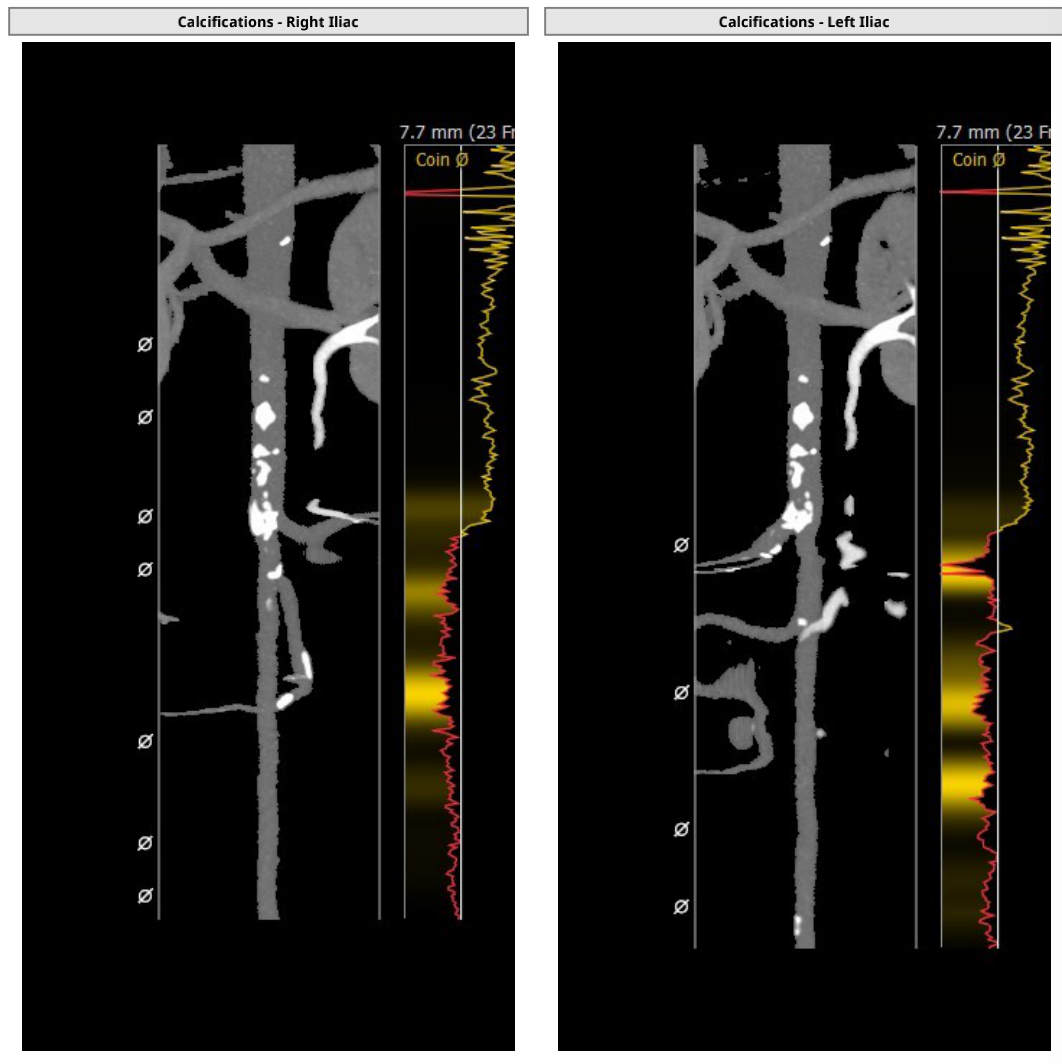

他指出,此次手术患者瓣膜病变较为严重,且患者长期卧床,身体素质较差,根本无法耐受外科开胸手术及经心尖TAVR手术,只能通过经股动脉TAVR手术来诊疗。而患者的血管评估结果又提示,患者股动脉迂曲、钙化严重且斑块较多,因此在选择瓣膜器械时,团队希望能尽可能减少对患者外周血管的损伤,瓣膜系统的输送鞘管越细越好。

仔细分析对比完临床上常见的几款瓣膜系统后,最终团队决定选用SAPIEN 3瓣膜。首先是因为SAPIEN 3瓣膜系统所使用的输送鞘管是临床上常用瓣膜产品中最细的一款。其次,CT评估出患者冠脉开口处存在风险,球扩瓣也能帮助降低TAVR手术对冠脉开口的影响。